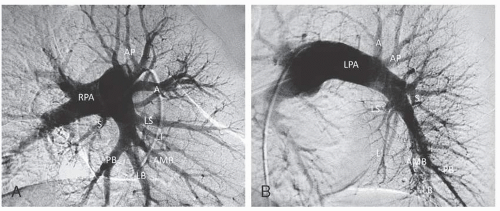

A : 20-30° RAO ; B : 35-40° LAO.